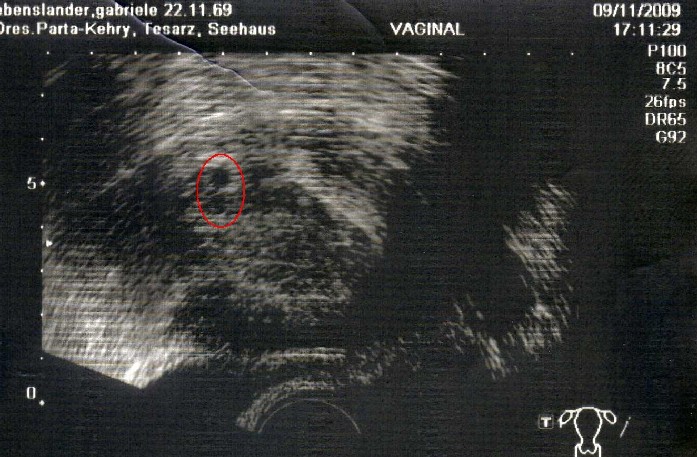

Leider entwickelte sich der HCG-Wert aber nicht ganz optimal und ich hab gestern meinem 1. US entgegengefiebert. Ich hab ehrlich gesagt mit allem gerechnet !

ABER ... alles ist gut

Man hat bei 5+4 eine schöne Fruchthöhle gesehen ... und darunter sogar nochmal etwas, was auch n Fruchthöhle sein könnte, aber es könnte auch ein Blutgefäß sein.

Ist das nicht der Hammer?

Anbei auch das Bild

Na, was meint ihr?